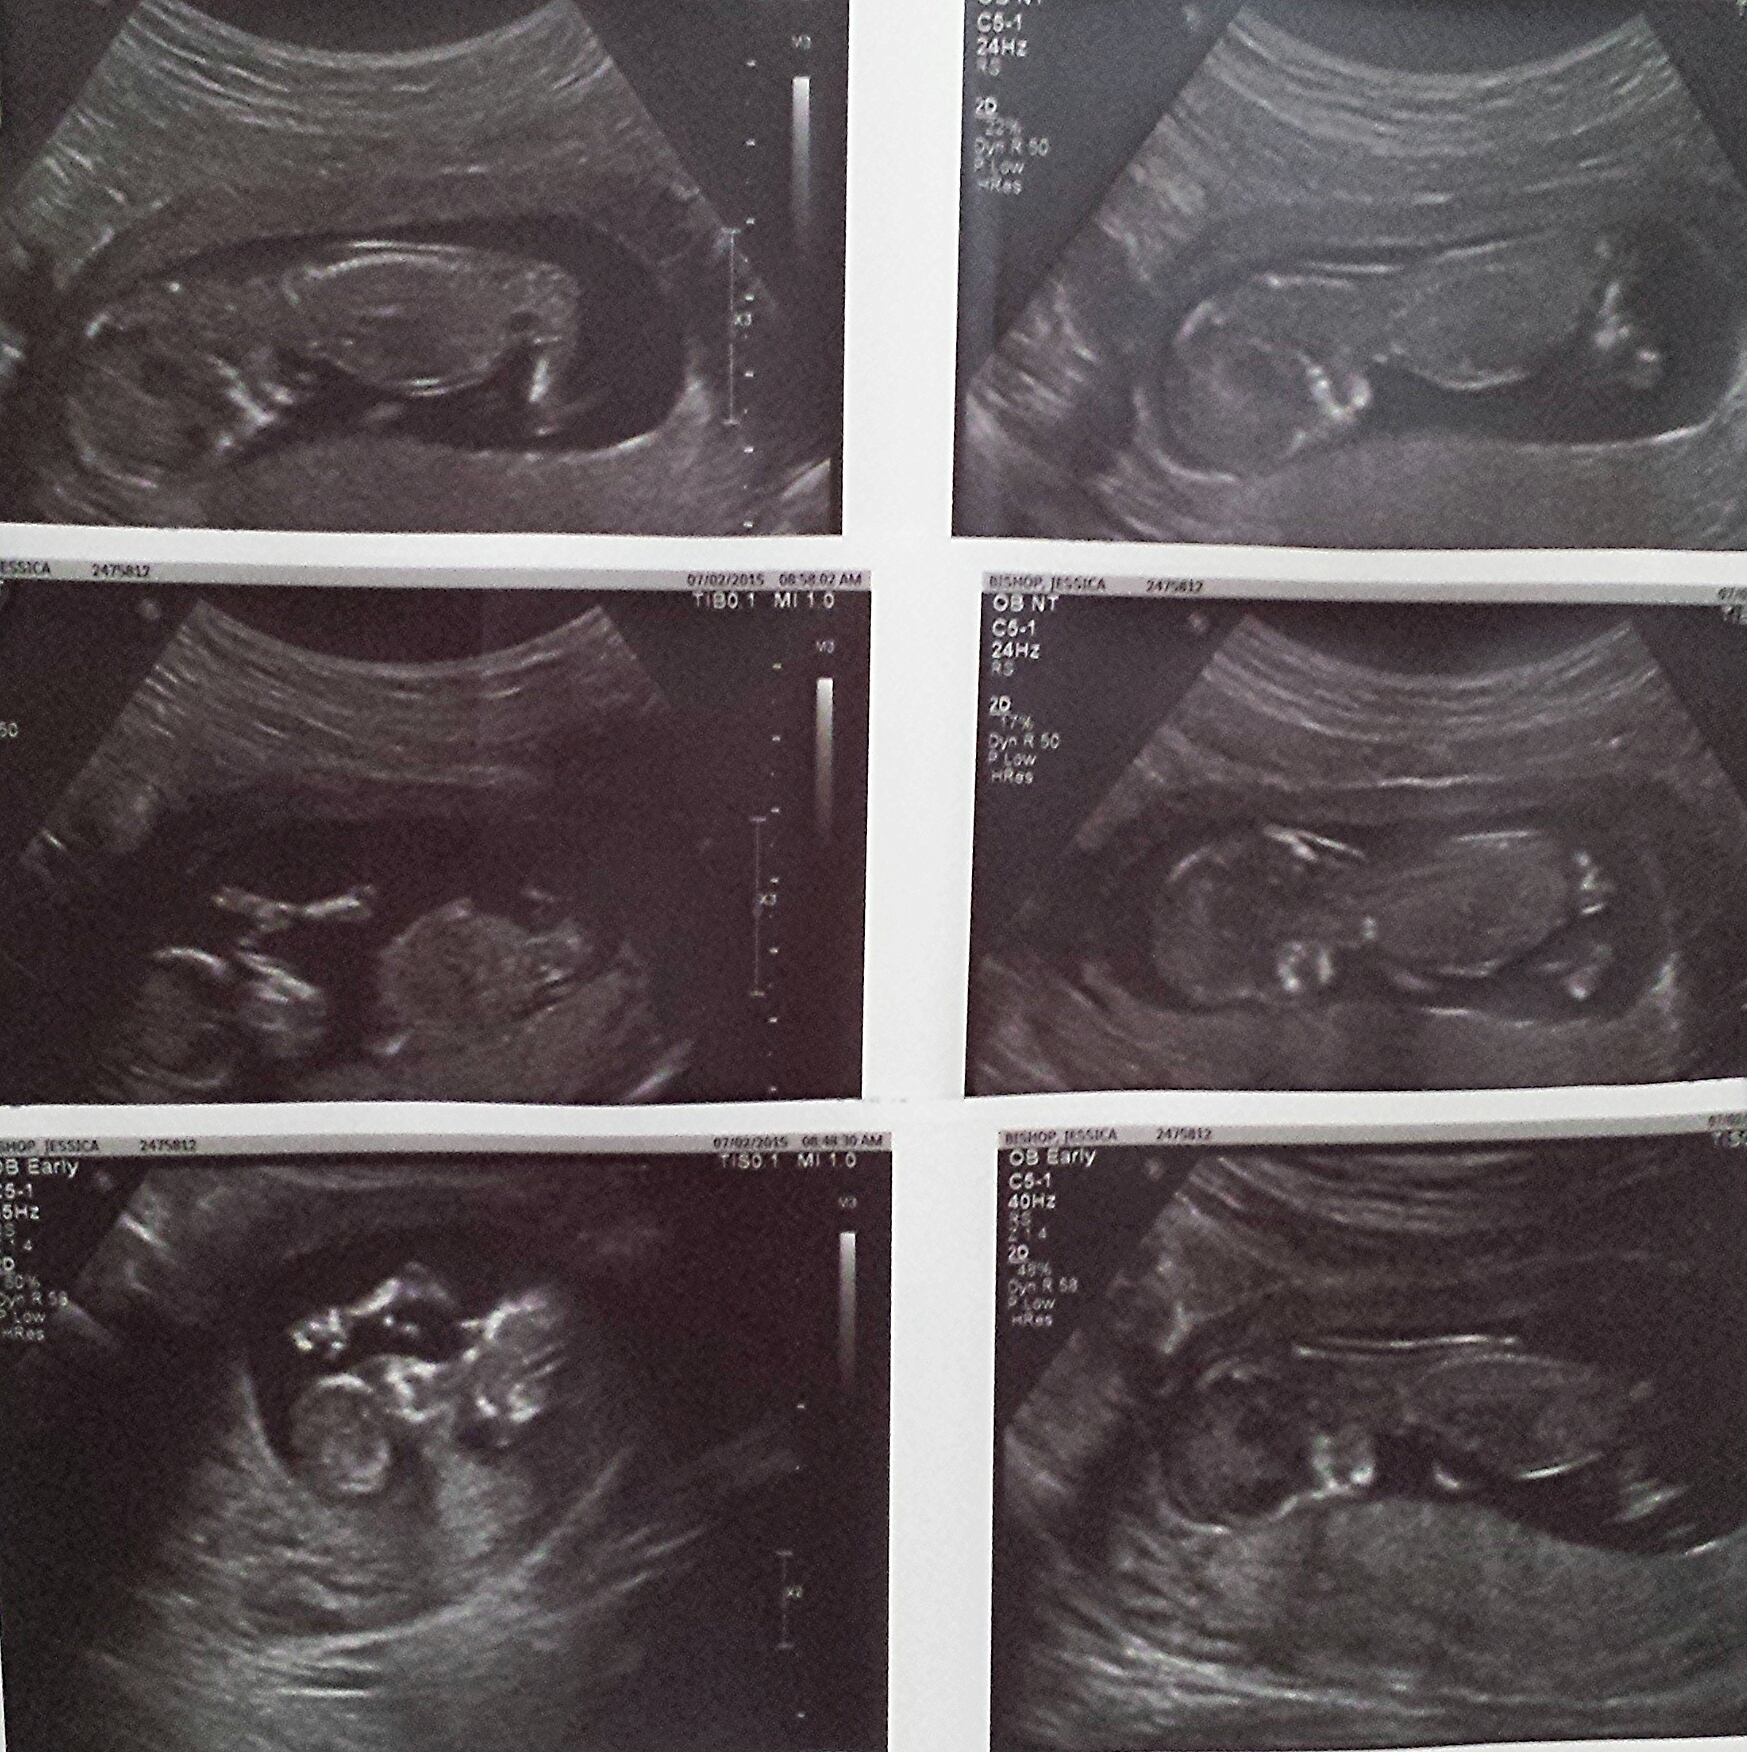

Here are my twins from my 13 week ultrasound. Both have strong heartbeats! One measuring at 13 weeks 4 days and the other 13 weeks 6 days. Tech made a guess and thinks they're boys!!

13 weeks 4 days, NT scan all looks fabulous. Heartbeat of 165. Baby was hiccuping and chillaxing! The baby is laying across my abdomen with its feet propped up in my uterus, nice and comfy in there! Placenta is also high, which is good because I was nervous about previa w/ earlier bleeding.

Here's our alien baby with its arms up towards its head. Had my NT scan today and the dr said measurements are falling well within the normal range. She also said because of that there is a 95% chance of no abnormalities. I am 12 weeks exactly. It was so great to see the baby!